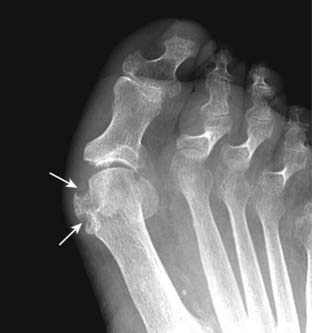

Figure 23-16 Gout.

Gout most commonly affects the metatarsal-phalangeal joint of the great toe, as in this patient. As an erosive arthritis, the hallmark of gout is the sharply marginated, juxtaarticular erosion which may have a sclerotic border (solid white arrows). The overhanging edges of gouty erosions have been called rat bites. The metatarsal-phalangeal joint space is not particularly narrowed, and there is no periarticular osteoporosis.